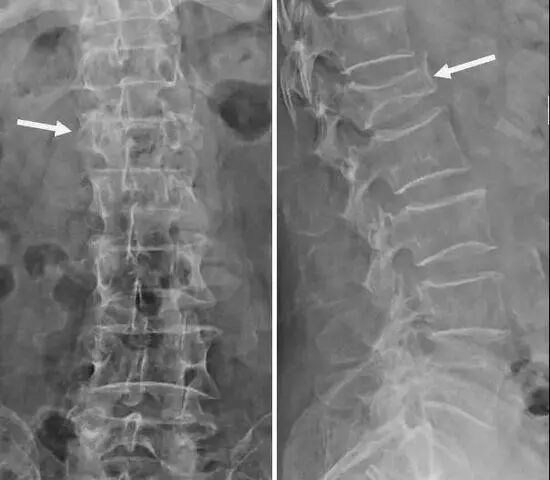

病例:患者李某,83歲,因不慎從樓梯摔落導(dǎo)致腰背部劇烈疼痛,活動(dòng)時(shí)加重,站立及行走困難,診斷為:腰1椎體爆裂性骨折、腰椎椎管狹窄。

腰椎正側(cè)位片

微創(chuàng)經(jīng)皮椎體成形術(shù)適用于大多數(shù)嚴(yán)重骨質(zhì)疏松并椎體壓縮性骨折患者。該患者椎體爆裂性骨折,從腰椎CT可看出,該椎體前方、側(cè)方多發(fā)骨折,且椎管內(nèi)存在骨塊壓迫,壓迫椎管將近1/3,單獨(dú)應(yīng)用該術(shù)式,骨折椎體無(wú)法很好恢復(fù)原先高度、易發(fā)生骨水泥泄漏,且后期椎管內(nèi)骨折塊可進(jìn)一步壓迫椎管,造成嚴(yán)重的神經(jīng)壓迫癥狀;微創(chuàng)經(jīng)皮釘棒內(nèi)固定術(shù)主要應(yīng)用于年輕的脊柱骨折患者,該術(shù)式相對(duì)于開放釘棒內(nèi)固定術(shù),具有創(chuàng)傷小、出血少、手術(shù)時(shí)間短等優(yōu)勢(shì)。